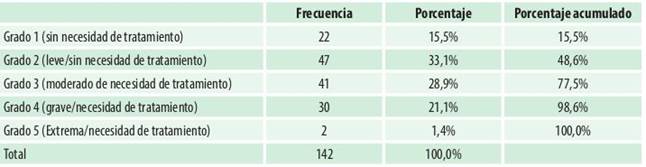

Con respecto al Componente de Salud Dental el grado de necesidad de tratamiento de ortodoncia fue de 15,5% grado 1, sin necesidad. El 33,1% fue identificado como grado 2, leve necesidad de tratamiento. El 28,9% fue identificado como grado 3, moderada necesidad de tratamiento. Es decir el 77,5% de los evaluados se encontraron dentro del límite de necesidad de tratamiento, el resto mostro grave y extrema necesidad de tratamiento de Ortodoncia (Tabla 3).

El análisis de las diferentes características oclusales en forma clínica y haciendo el registro de las alteraciones por parte del profesional, teniendo en consideración una escala de medición previamente establecida, se denomina el Componente de Salud Dental del Índice de Necesidad de Tratamiento de Ortodoncia, hemos podido observar un porcentaje 33,1% de leve, 28,9% moderada y 21,1% de grave necesidad de tratamiento de ortodoncia, componente identificado por el profesional al momento de hacer la evaluación clínica. El Componente de Salud Dental se basó en el análisis de distintas características oclusales por parte del profesional, y el registro de las alteraciones de la misma, dentro de una escala. Al analizar los resultados que nos arroja el Componente de Salud Dental, podemos manifestar que es más confiables, porque es realizado por el Odontólogo sobre un análisis objetivo de las condiciones de salud oral del escolar, quien a los 12 años ya presenta todas las piezas dentales permanentes erupcionadas, en quien se puede apreciar la presencia de maloclusiones dentales y esqueléticas. Se puede hacer el diagnóstico sin temor a equivocarse.